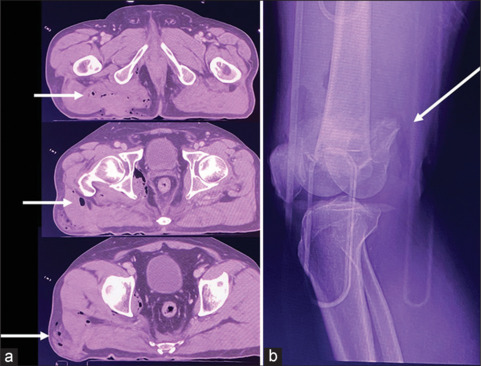

Gluteal Degloving Injury: A Form of Dashboard Injury.

臀部脱手套损伤:一种仪表板损伤。